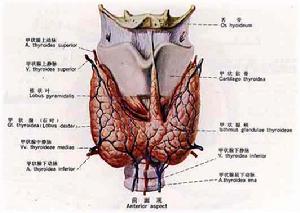

甲狀旁腺

甲狀旁腺

甲狀旁腺

甲狀旁腺